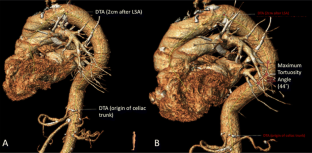

Fig. 4

Fig. 5